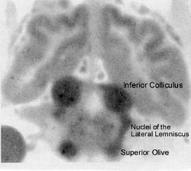

Sokoloff (1981) discussing measurements of regional

glucose uptake stated, “the inferior colliculus is clearly

the most metabolically active structure in the brain”

[2]. Figure 12 is an autoradiographic photo (from an

article by Kety 1962) that shows the high rate of blood

flow in the inferior colliculus [3].

Figure 12 -

From Kety (1962) with permission from Columbia University Press